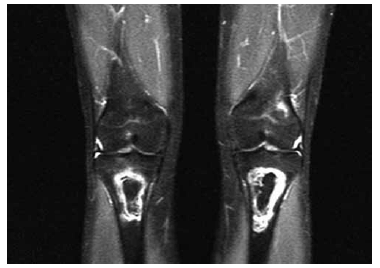

Paciente fez tratamento de leucemia e agora está com dor nos joelhos. A ressonância dos joelhos demonstra:

O diagnóstico mais provável é: